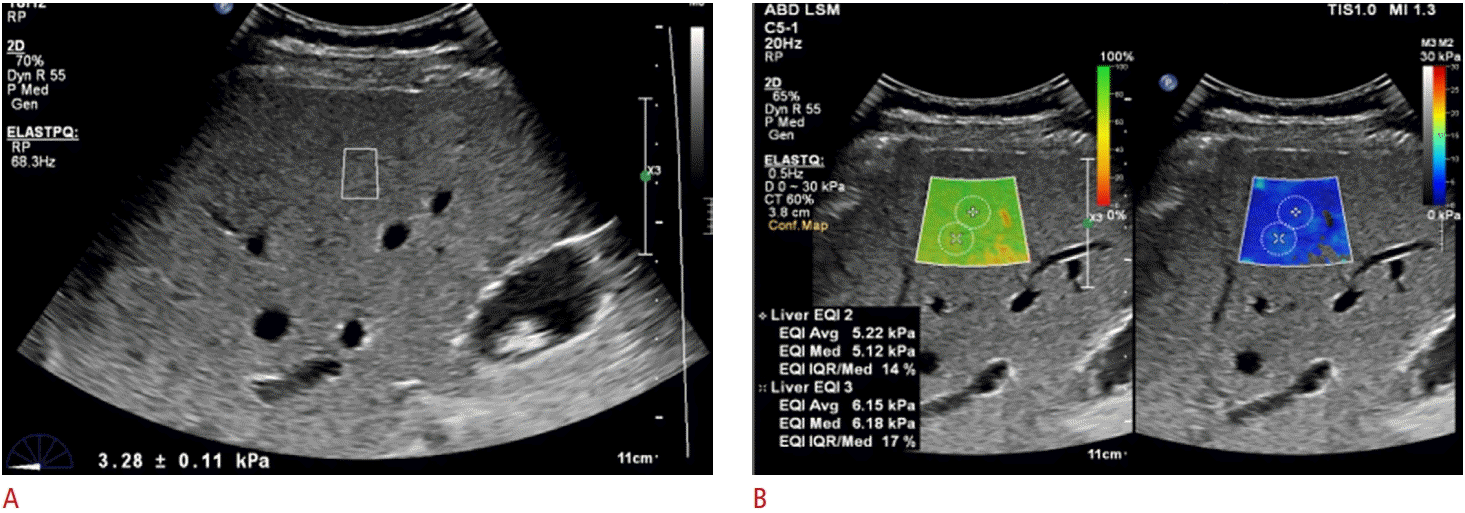

For LS measurements using ElastPQ, a measuring box of 1.5 cm×0.5 cm was placed in the right anterior section of the liver, avoiding large vessels and bile ducts (Fig. 2A). As ElastQ Imaging was performed, a large, trapezoid-shaped, colored elastographic box was placed in a similar position of the liver with simultaneous use of the confidence map, which shows areas of high confidence in green and areas of low confidence in red. Two or three round ROIs (diameter, 1 cm) were placed within the third elasticity map after passing the first and second elasticity maps (Fig. 2B) [29-31]. To obtain 10 valid measurements, 4-5 breath holds were required when using ElastQ Imaging, whereas more than 10 breath holds are generally required for ElastPQ.

Fig. 2.

Liver stiffness (LS) measurements using ElastPQ (A) and ElastQ Imaging (B).

A. For LS measurements using ElastPQ, a measuring box (1.5 cm×0.5 cm) is placed in the right anterior section of the liver, avoiding large vessels and bile ducts. B. For LS measurements using ElastQ Imaging, a large, trapezoid-shaped, colored elastographic box (right) is placed in the right anterior section of the liver with simultaneous use of the confidence map (left). Regions of interest (diameter, 1 cm) are placed within the elastographic box in the area where the confidence map is green.